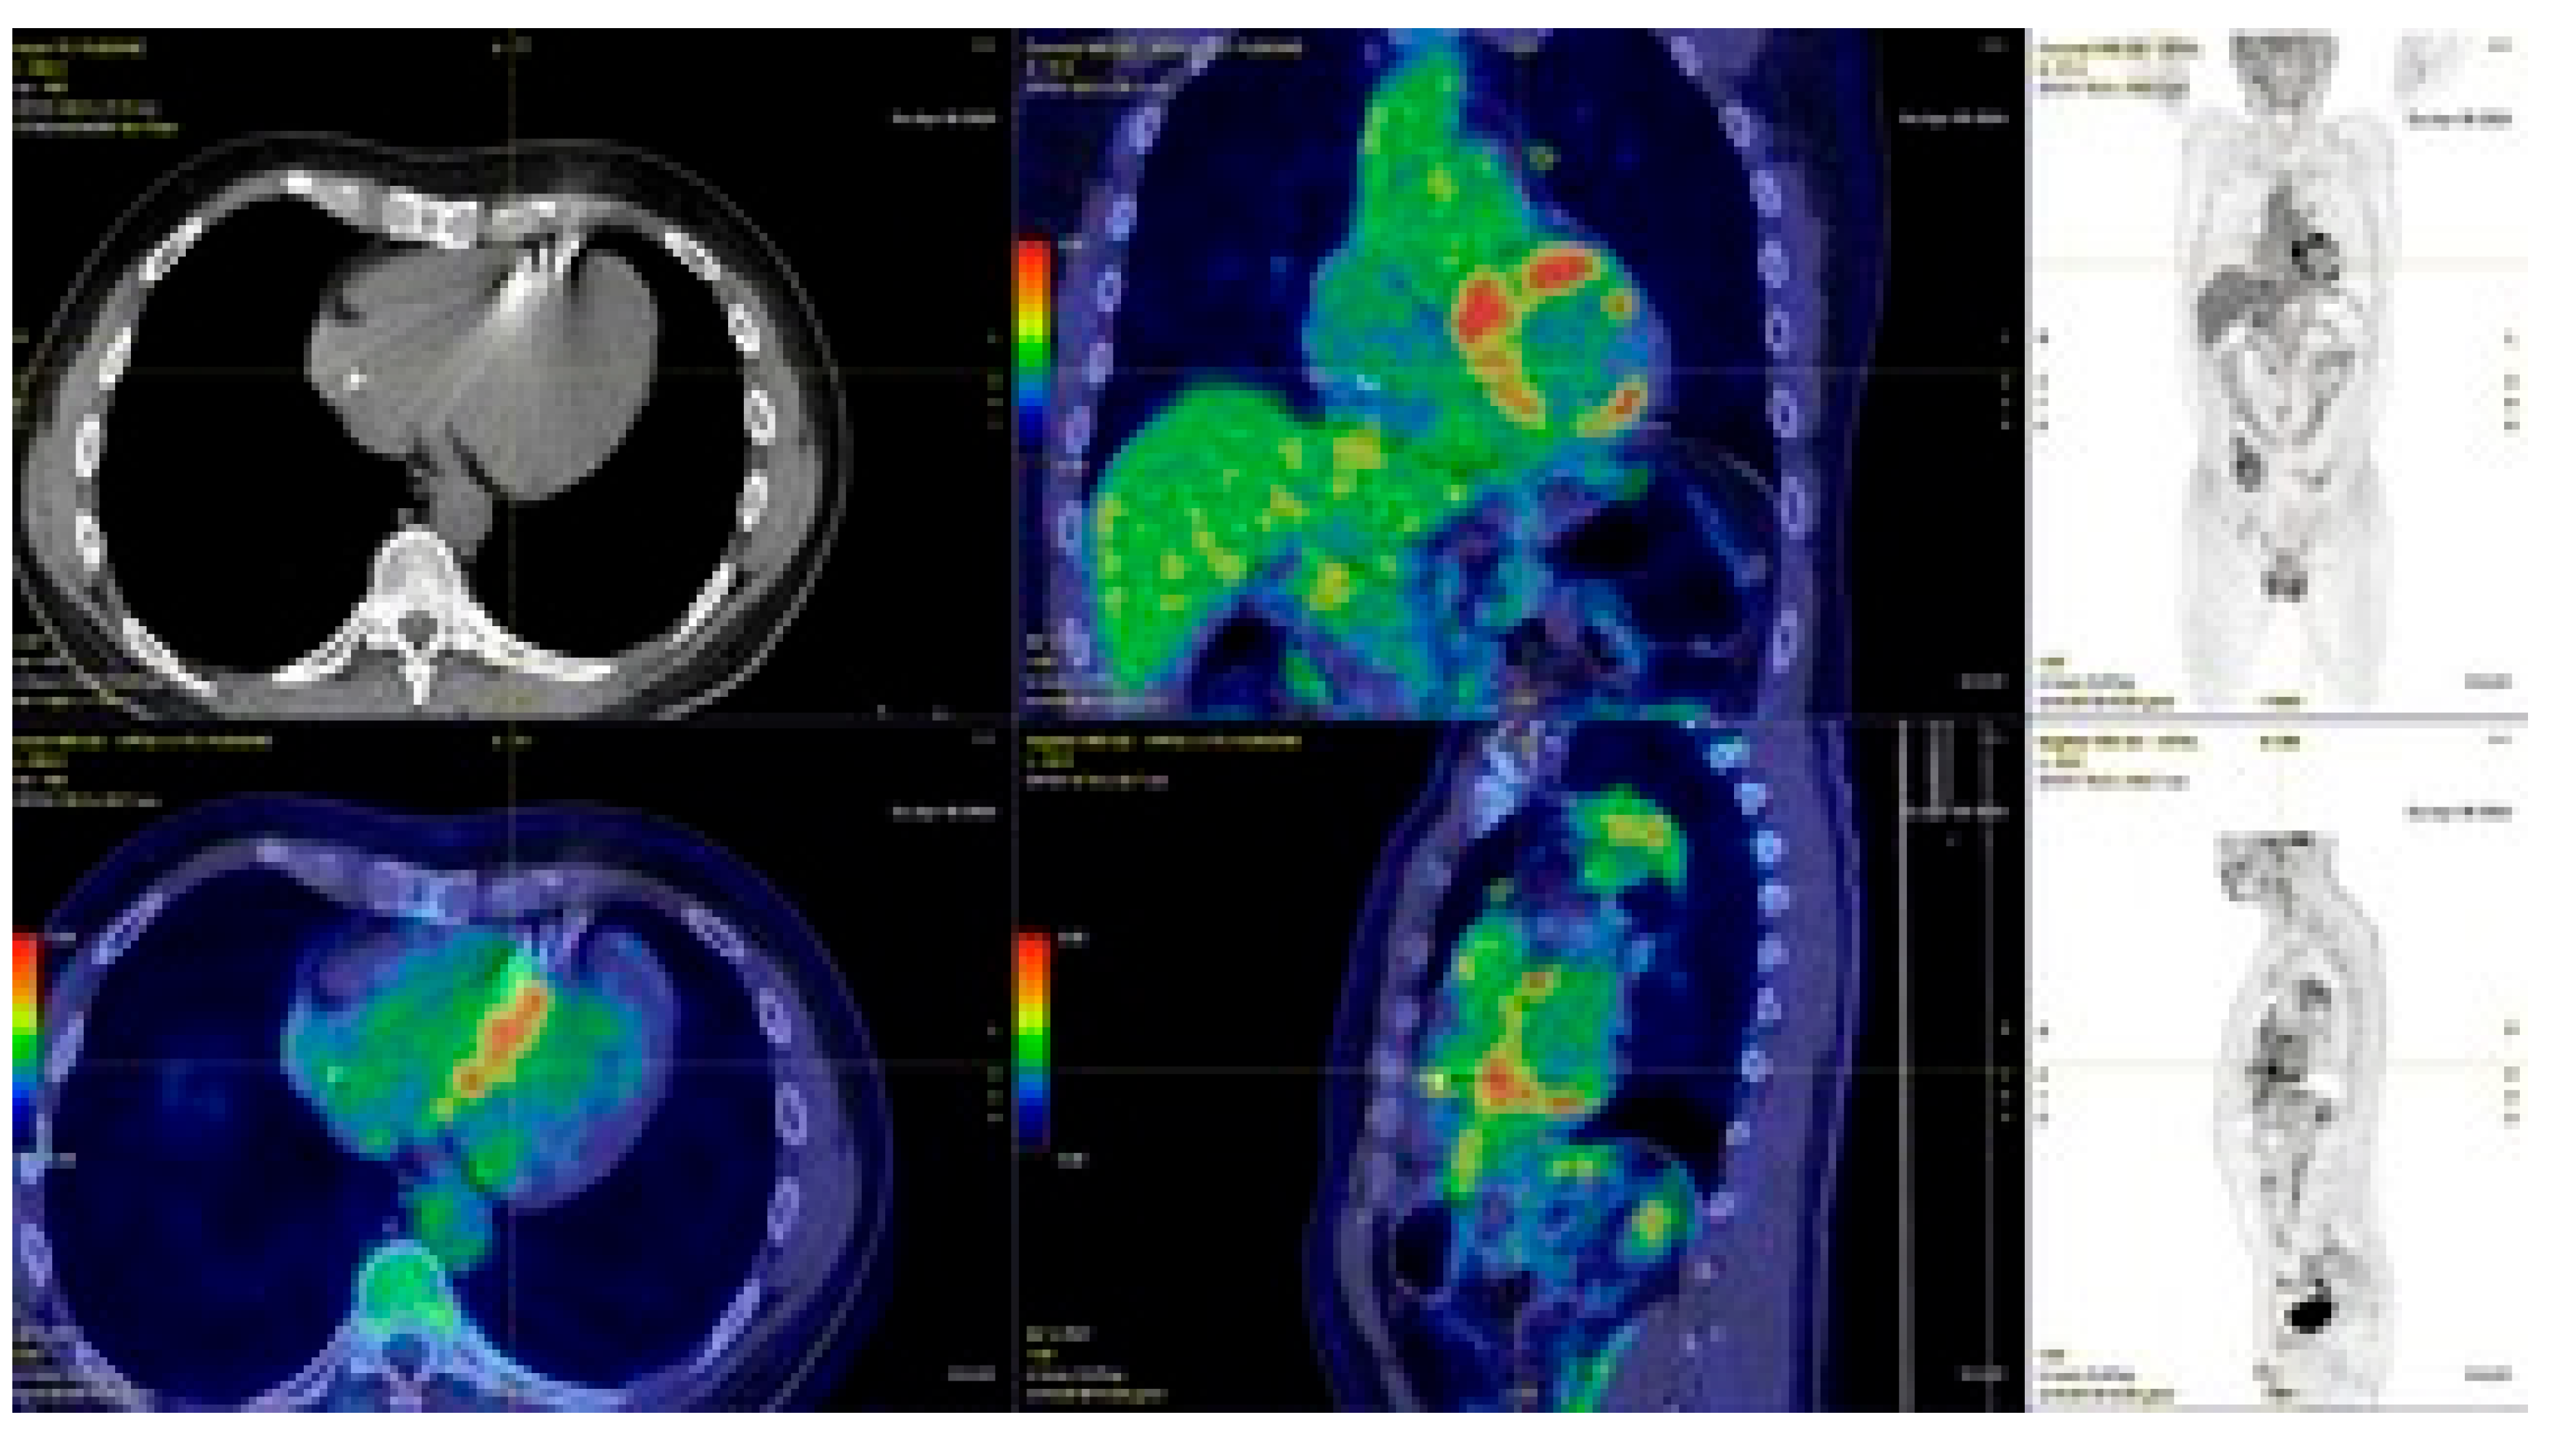

4.4. Athlete with Ventricular Arrhythmias and Late Enhancement on Cardiac MRI Suspected for Cardiac Sarcoidosis